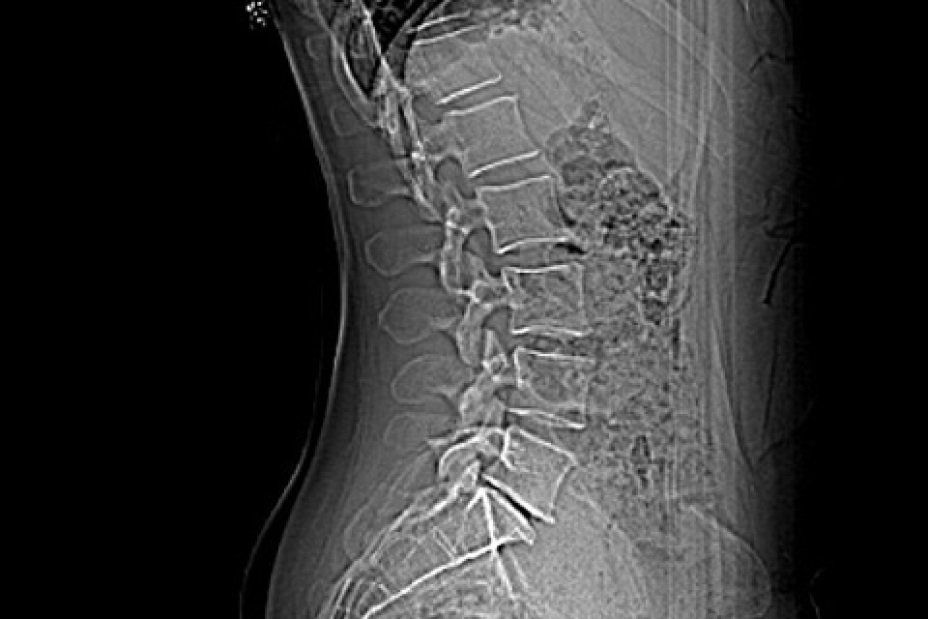

Die Krankheitsentstehung des Facettensyndrom ist im Zusammenhang mit anderen degenerativen Wirbelsäulenerkrankungen zu sehen. Der Verschleiß der Bandscheiben beginnt schon in den 20iger Jahren eines Menschen. Es kann zur Bandscheibenvorwölbung oder zum Bandscheibenvorfall kommen. Der zunehmende Wasserverlust der Bandscheibe führt zu einer Höhenabnahme des Zwischenwirbelkörperabschnittes (Osteochondrose). Die Folgen sind eine Überlastung der kleinen Wirbelgelenke.

Grund- und Deckplatten der Wirbelkörper werden durch die erniedrigte Bandscheibe mehr belastet. Der Körper reagiert darauf mit einer Knochenverdichtung im Bereich dieser Strukturen, was röntgenologisch zu erkennen ist.

Die sich schleichend entwickelnde Instabilität der Wirbelsäule versucht der Köper dahingehend zu begegnen, dass knöcherne Anbauten an den Wirbelkörpern produziert werden, die nach Halt in der Umgebung suchen.

- Bei sehr weit fortgeschrittener Instabilität, kann sich eine verschleißbedingte Verkrümmung der Wirbelsäule ausbilden, wodurch die Statik der Wirbelsäule weiter geschwächt wird (degenerative Skoliose).

Die Behandlung wird grundsätzlich in örtlicher Betäubung mit sehr feinen Nadeln vorgenommen. Der Patient liegt auf dem Bauch auf dem CT-Tisch. Zur genauen Höhenlokalisation der Schmerzstelle wird auf den Rücken ein Metallstreifen /Büroklammer geklebt. Ein so genanntes Topogramm, also eine Übersichtsaufnahme des entsprechenden Wirbelsäulenabschnittes wird angefertigt. Jetzt kann auf dem computertomographischen Schnittbild die Schmerzstelle lokalisiert werden. Auf dem Bearbeitungsmonitor können dann der exakte Eintrittspunkt der Nadel, der Winkel und die Tiefe, sowie die Stelle. in der gespritzt werden soll, ermittelt werden. All diese Parameter werden anschließend mit einem Laserpunkt auf dem Patienten dargestellt. Gefolgt von einer örtlichen Punktion nach steriler Säuberung der Haut kann die feine Punktionsnadel, die eine millimetergenaue Skalierung aufweist, am Schmerzpunkt platziert werden. Es folgt die CT- Kontrollaufnahme zur Dokumentation der exakten Nadellage. Um das Verteilungsmuster des zur verabreichenden Medikamente feststellen zu können, wird eine kleine Menge von verdünntem Kontrastmittel gespritzt. Dann werden Medikamente um die Nervenwurzeln verabreicht (PRT= Periradikuläre Schmerztherapie).